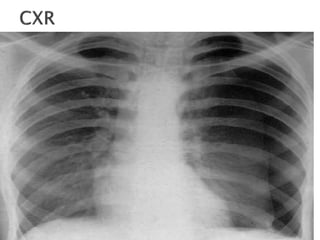

 Respiratory distress

 Tachypnea

 Asymmetric lung expansion.

 Decreased tactile fremitus

 Hyperresonance on percussion

 Distant or absent breath sounds